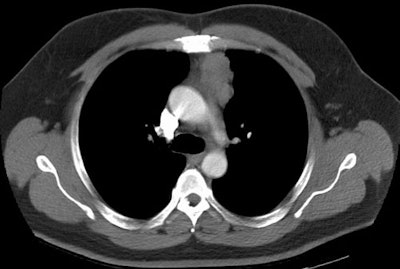

Invasive Thymoma:

The images below demonstrate an invasive thymoma. The first image demonstrates an eccentric, lobulated anterior mediastinal mas. There is ill-defined increased density within the anterior mediastinal fat, as well as the presence of a borderline enlarged mediastinal lymph node adjacent to the mass. On the lower image, the mass lacks a well defined border and again noted is infiltration of the mediastinal fat. These features suggest an invasive thymoma. (Click on images to enlarge)